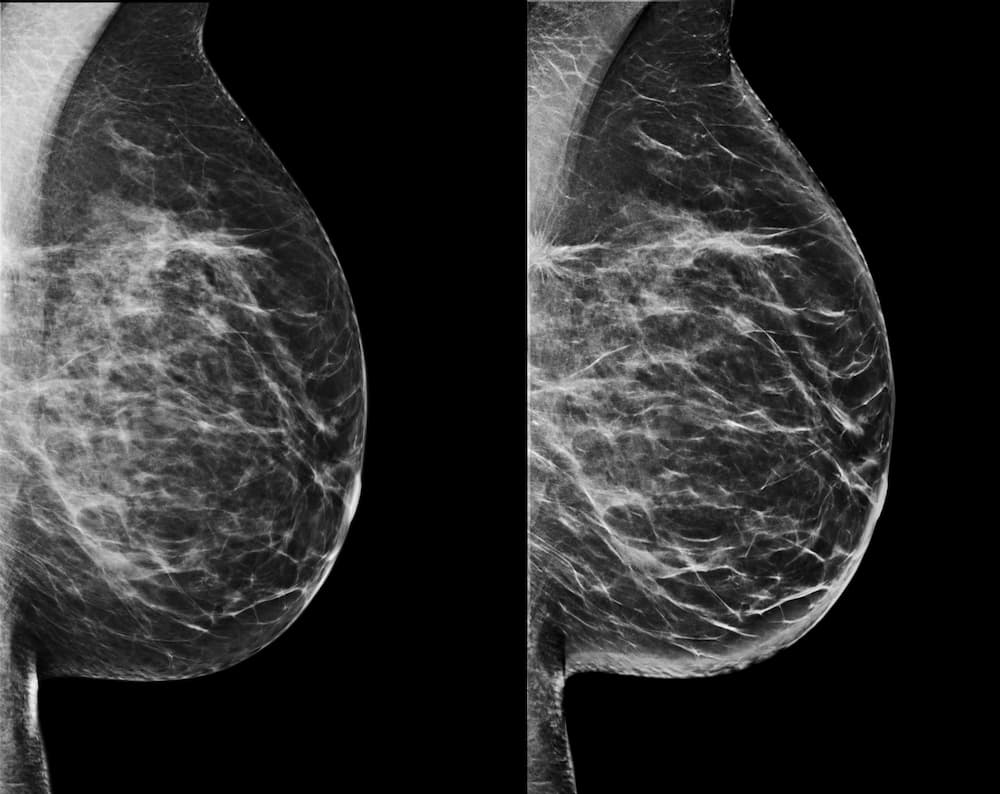

La mammografia è un esame fondamentale per la prevenzione del tumore della mammella, poiché è in grado di individuare lesioni di piccole dimensioni. Rappresenta quindi una tecnica di diagnostica per immagini consigliata a tutte le donne a partire dai 40 anni.

La mammografia è una tecnica di diagnostica radiologica che consente di rilevare lesioni mammarie in fase molto precoce ed è consigliata a tutte le donne a partire dai 40 anni. L’apparecchio radiologico che consente di effettuare l’esame è il mammografo che, nelle versioni aggiornate, permette di utilizzare la tecnica di imaging tridimensionale (TOMOSINTESI), ovvero la ricostruzione di immagini volumetriche della ghiandola mammaria, metaforicamente affettando l’organo in strati.